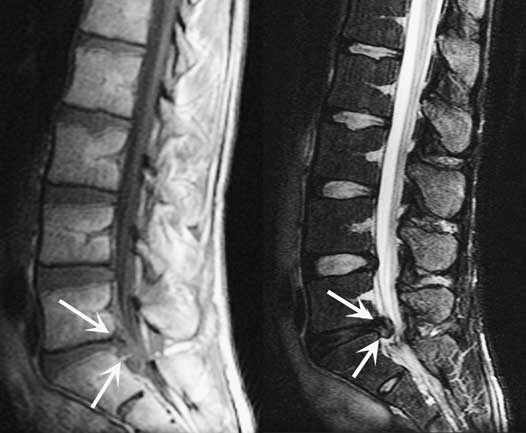

КТ и МРТ

Компьютерная и магнитно-резонансная томография — самые информативные диагностические методы для обнаружения протрузии. На полученных трехмерных изображениях хорошо визуализируются смещение диска за границы позвоночного канала. На выпячивание указывает уменьшение ширины между его краями по сравнению с основанием.